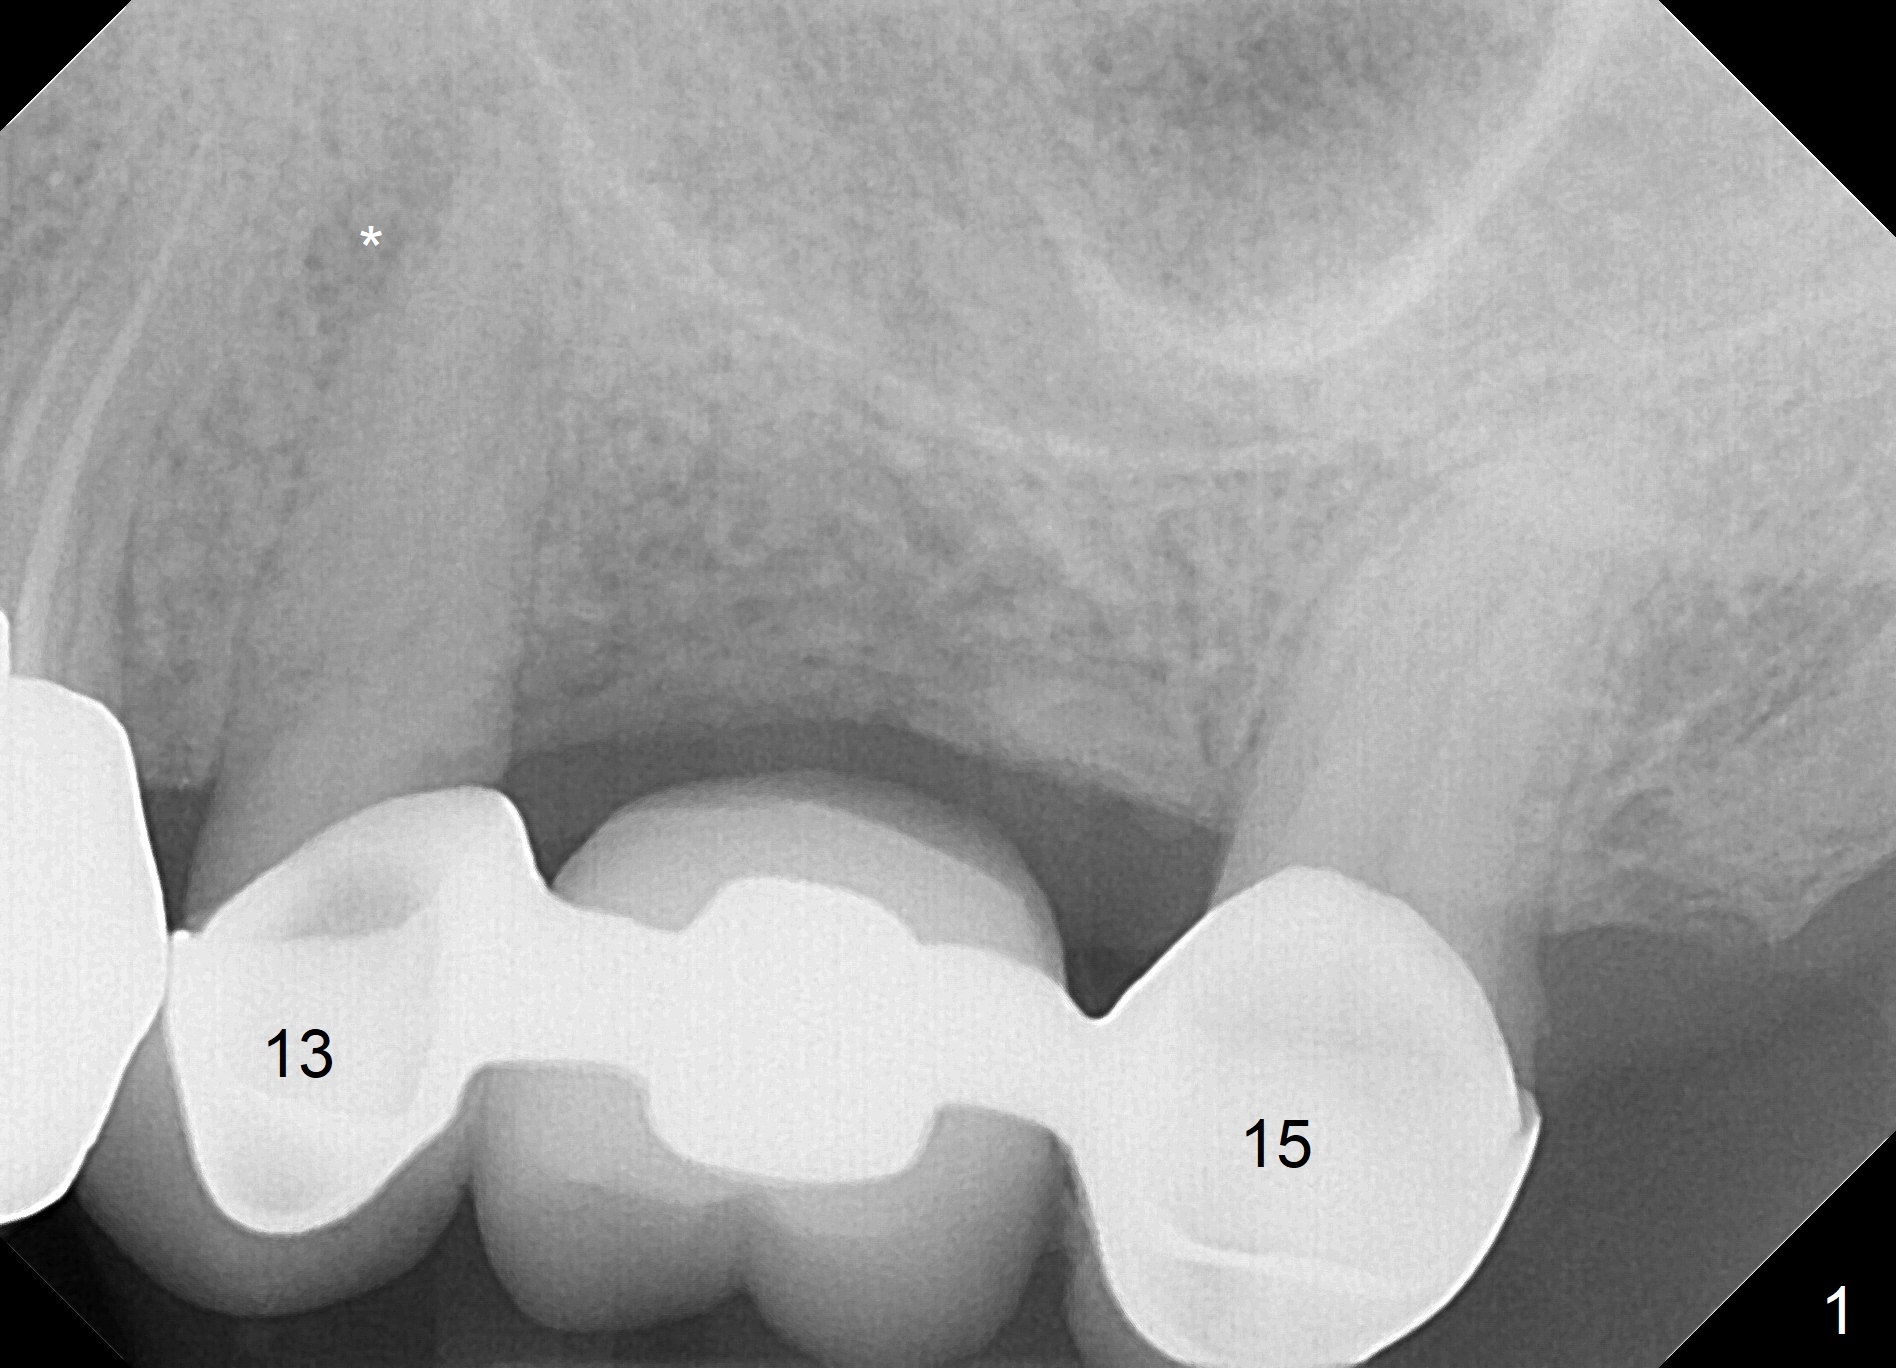

Implant Site Next to PARL

A 75-year-old man came to our office with symptom related to #13-15 FPD 2 months ago (Fig.1). Note periapical radiolucency (PARL, *) associated with the tooth #13. He has a RPD to replace #2 and 3. Last Friday, the crown and post at #12 dislodged (Fig.2). To reduce infection from the neighboring tooth (*), osteotomy will be established in the mesial slope of the socket (red line). The RPD has clasps at #4; the immediate provisional should be wide enough to cover the socket, while it must be skinny enough coronally to avoid contact when the patient puts on and takes off the RPD. The 1st premolar is still in cosmetic zone. If the implant is placed buccal, use a gold-coated abutment. Return to Upper Premolar Immediate Implant, IBS, Clindamycin Xin Wei, DDS, PhD, MS 1st edition 08/25/2017, last revision 11/10/2018